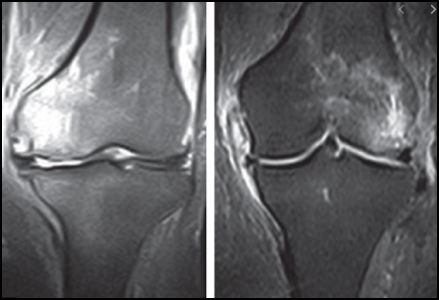

4. Indagini di secondo livello: RMN, TC, SCINTIGRAFIA OSSEA.

La Risonanza Magnetica Nucleare, non solo accerta quanto emerso nei precedenti test diagnostici, ma permette anche di chiarire l'entità della degenerazione e dell'assottigliamento a carico delle cartilagini di femore e tibia, di evidenziare la presenza di edema midollare, di sinovite e di versamento articolare. Le informazioni derivanti dalla risonanza magnetica nucleare delle ginocchia consentono al medico curante di stabilire il trattamento più adeguato.